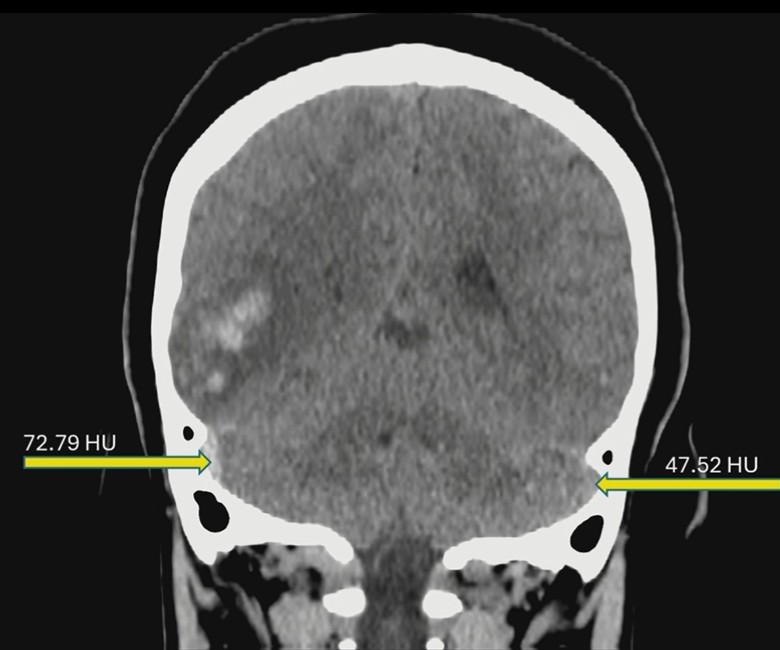

ER Headache? Don’t Miss the Sinus.

Rads often encounter normal non-contrast head CTs for headaches, but the real art lies in identifying dural venous sinus thrombosis (DVST) before that CTA is even ordered.